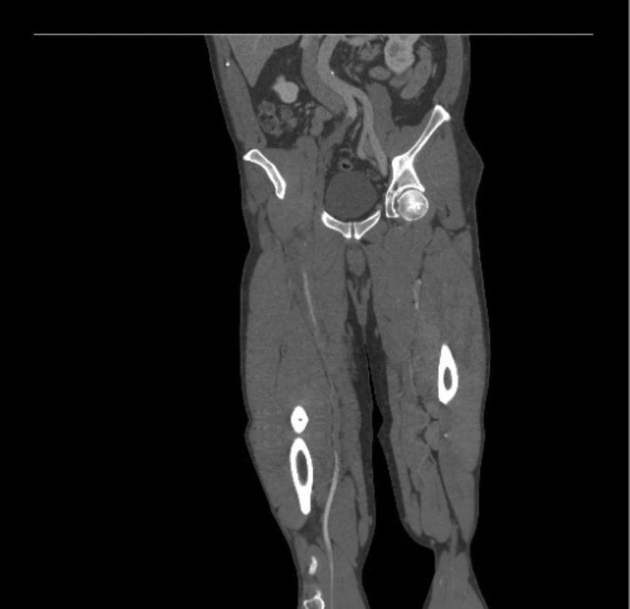

Fig 2.

Coronal view of computed tomography angiography (CTA) showing lack of contrast opacification in the mid right common iliac artery (CIA).